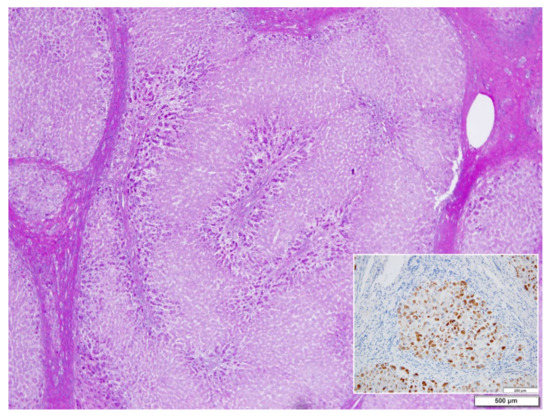

In ZZ patients from groups 2 and 4, the positivity was mainly restricted to zone 1 (periportal) hepatocyte in the form of PAD positive globules (Figure 5) filling up the entire cytoplasm (type I positivity), or unevenly distributed in the intralobular hepatocytes with type II positivity (Figure 5 inset).

On immunostaining, HHHS and Pi ZZ patients show a similar pattern especially in the cirrhotic stage. Hepatocytes show mainly type I positivity, but type II can be observed in some areas of the nodules (Figure 15).

Figure 5. Pi ZZ explanted liver. A mixed type (uni- and multilobular) cirrhosis. PASD inclusions are present in zone 1 hepatocytes, separated from the connective tissue of the portal tracts by edema. PAD × 1.25. AAT inclusions fill up the entire hepatocytic cytoplasm in a small nodule. A few positive cells are scattered in the central part (Inset. AAT polyclonal immunostaining × 60).

Figure 15. HHHS cirrhotic liver. Fibrinogen inclusions are present in all parenchymal nodules. The immunoreaction appears in the whole cytoplasm. In the central part of the smallest nodule, the positivity appears at the periphery of the cells, beneath the plasma membrane (polyclonal fibrinogen immunostaining × 2).